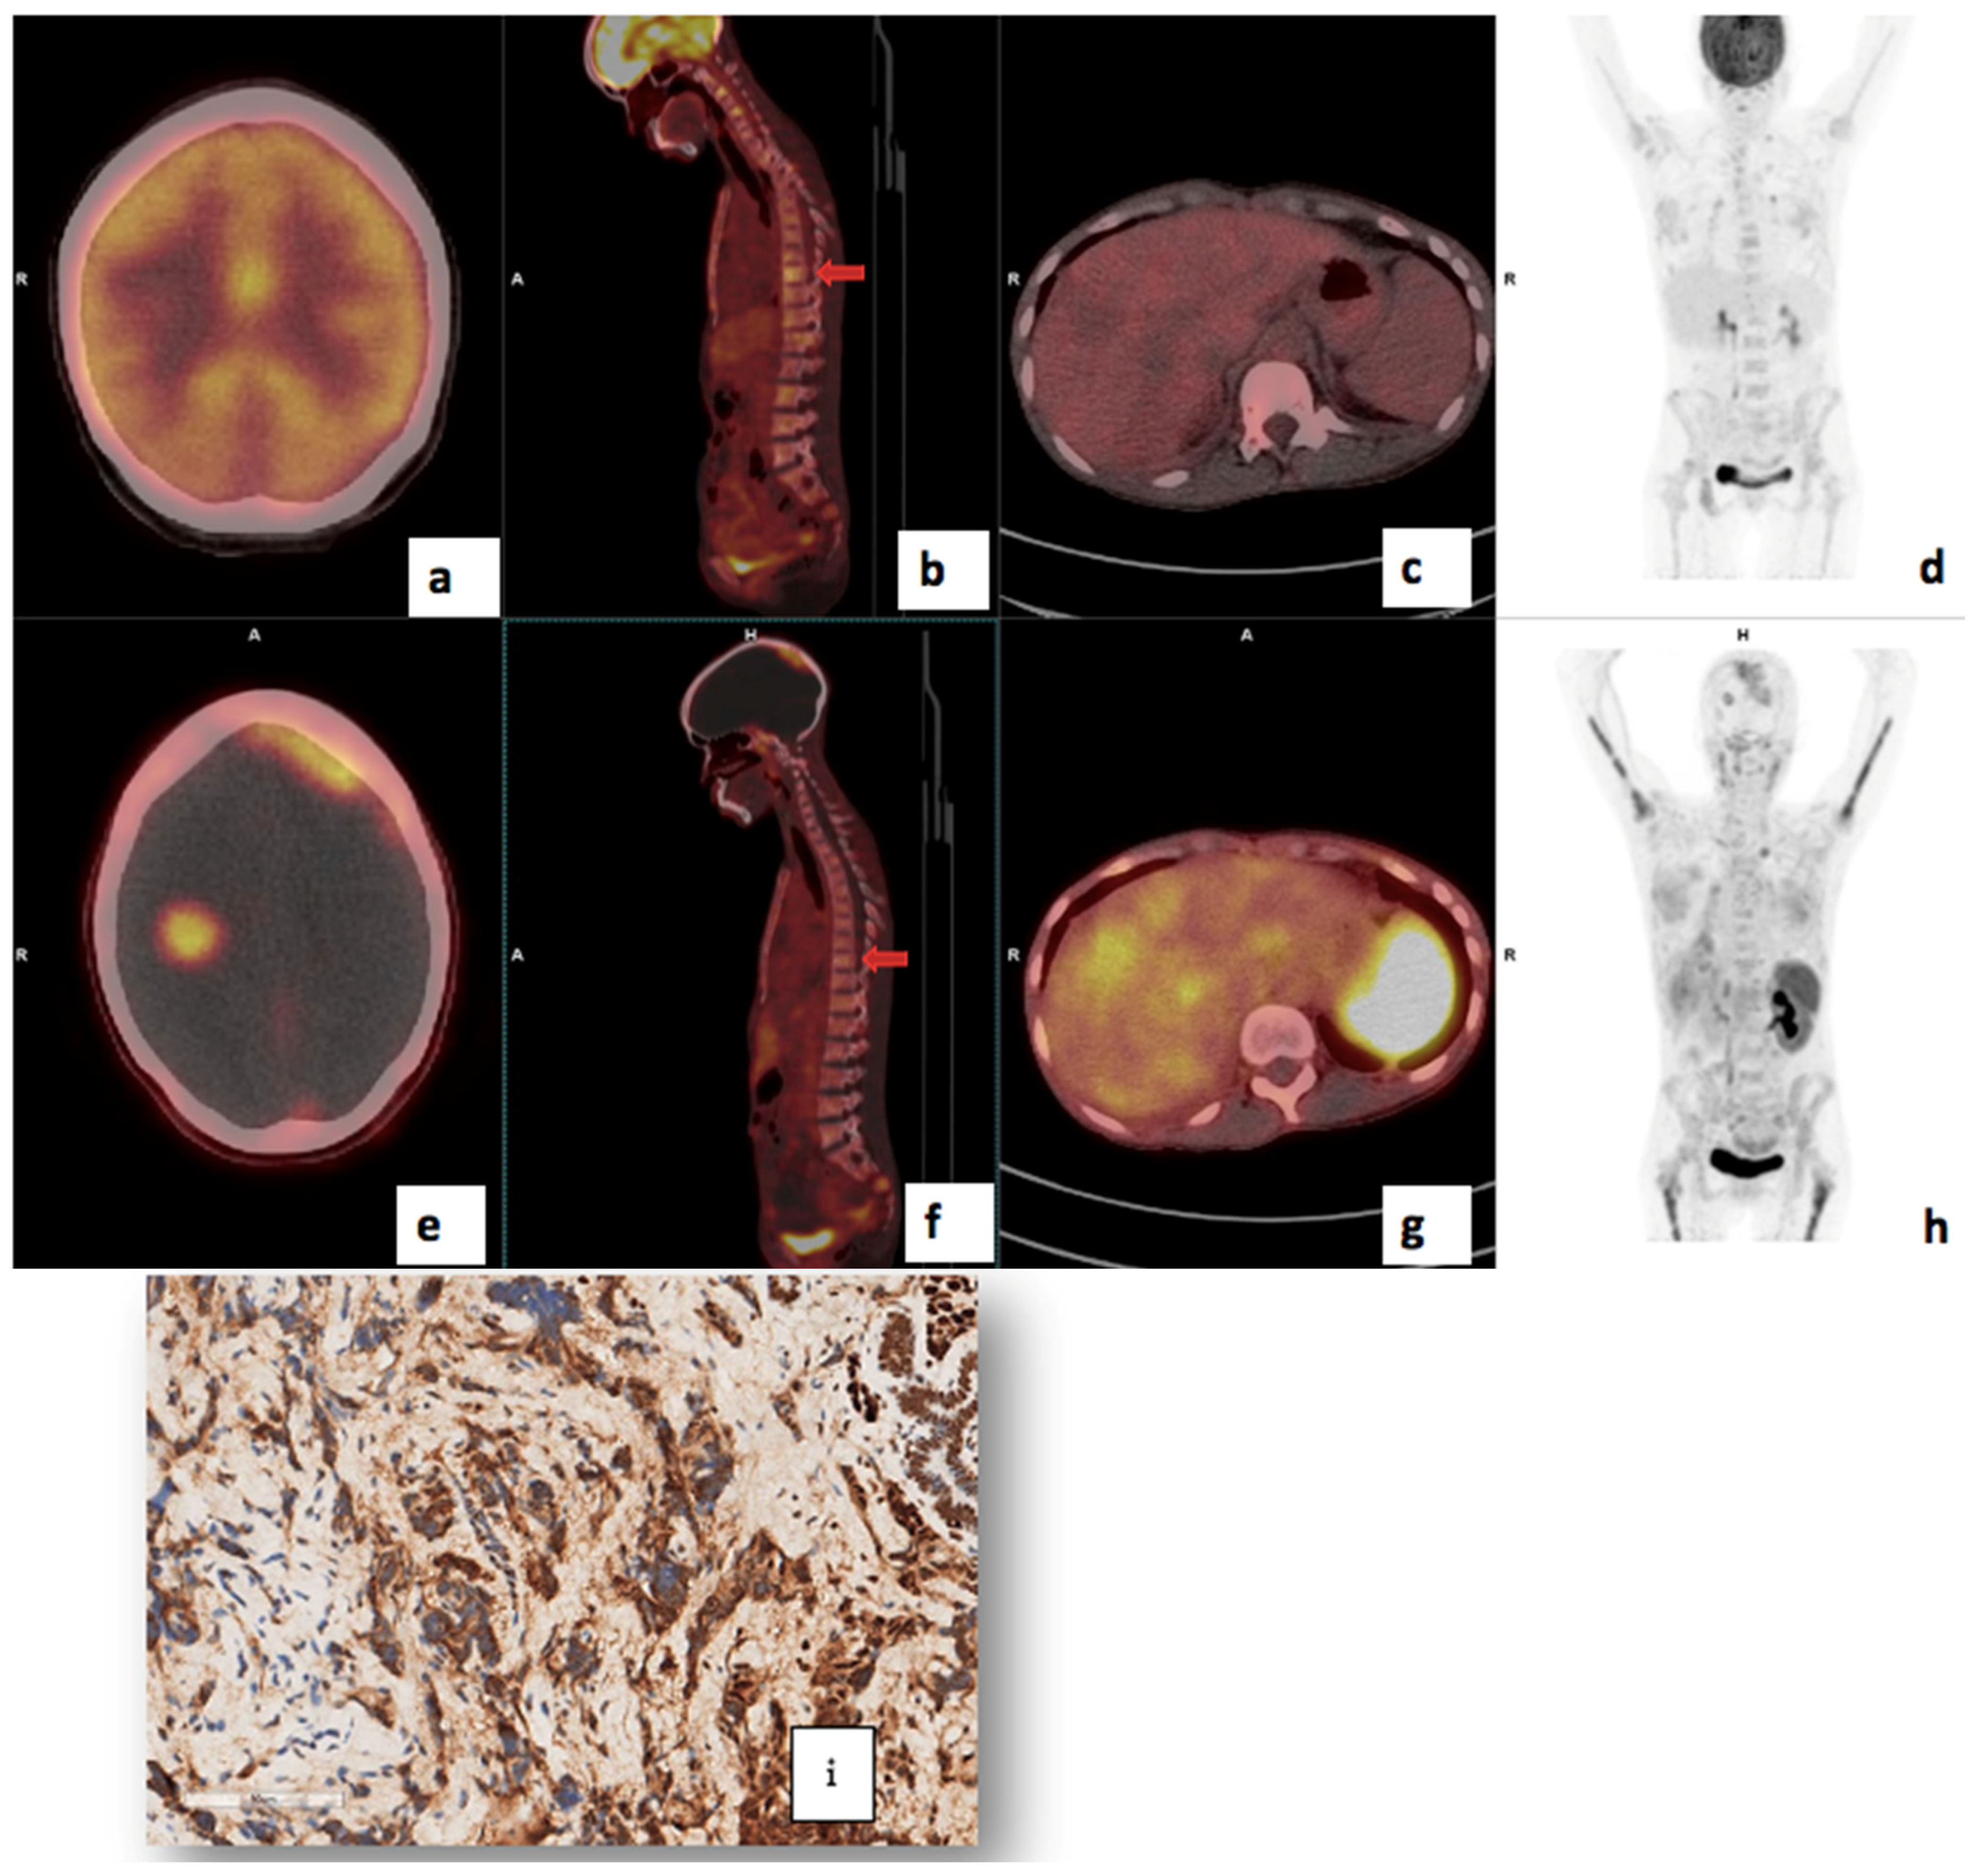

Figure 3.

Shows 68Ga-Pentixafor (a–d) and FDG (e–h) images of a 56-year-old with TNBC T4bN2M0, Bloom Richardson Grade III Ki67 50%, showing intense uptake on both tracers in the right breast (a,e) and axillary lmph nodes (b,f). SUVmax was 36.85 on 68Ga-Pentixafor and 77.94 on 18F-FDG. The TBRs for FDG and Pentixafor were 19.5 and 17.4 in the primary and 7.6 and 7.2, respectively, in the axillary lymph nodes. The patient also has HIV with reactive inguinal lymph nodes, demonstrating mild uptake on both tracers (d,h).

A 41-year-old with bilateral T4bN2M0 luminal B breast cancer, Bloom Richardson Grade II, HIV-positive, Ki67 30%, and metastasis to the lungs, bone, liver (c,g) and brain (a,e). Using 68Ga-Pentixafor, mild uptake was observed in the breast primary, SUVmax 4.6 (d,h). The brain metastasis were more clearly visualised on 68Ga-Pentixafor imaging (e) compared to 18F-FDG (a) due to the absence of physiological brain uptake with Pentixafor. The liver metastasis are also detected on Pentixafor (g) and not seen on FDG (c). However, the skeletal metastasis are seen on FDG (b) and not Pentixafor (f) likely due to higher physiological bone marrow uptake on Pentixafor (h). CXCR4 IHC showed strongly positive staining in 60% of the tumour cells (i).